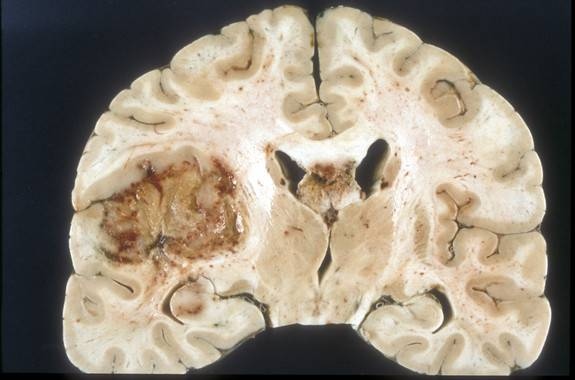

El glioblastoma es la manifestación más agresiva de los tumores cerebrales. Debido a la elevada capacidad invasiva y su crecimiento descontrolado infiltrativo, es un tumor especialmente difícil de tratar. Actualmente, el tratamiento establecido para los pacientes con estos tumores consiste en la combinación de cirugía (cuando es posible), radiación y quimioterapia.

Los científicos han observado que las células de este tipo de tumor albergan un defecto intrínseco común que consiste en una incapacidad para degradar su material genético durante la apoptosis, la forma más importante de muerte celular programada inducida por la radioterapia y por agentes quimioterapéuticos. Los resultados se publican en la revista Neuro-Oncology.

Este defecto está relacionado con una enzima: la endonucleasa activada por caspasas, DFF40 / CAD. Esta enzima, esencial para que la célula degrade su ADN durante la apoptosis, aparece disminuida y localizada de manera incorrecta dentro de las células tumorales en comparación con las no tumorales.

Los investigadores han observado que la sobreexpresión de la enzima permite a las células de glioblastoma degradar correctamente su contenido genómico, de acuerdo a lo que se espera de una muerte celular apoptótica.

A pesar de los esfuerzos realizados durante la última década, hasta ahora no se había encontrado ningún defecto genético ni bioquímico común en células de glioblastoma. El descubrimiento, los bajos niveles de expresión de la enzima endonucleasa DFF40 / CAD observados y la deficiencia para degradar y compactar de forma adecuada su material genético, constituyen un potencial marcador molecular en este tumor.